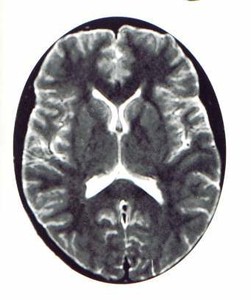

Речовина мозку на знімках позначено сірим кольором, а рідина - білим. Зліва - нормальна ширина рідинних порожнин (шлуночків) мозку

Праворуч - шлуночки переповнені рідиною, внутрішньочерепний тиск підвищений, є головний біль